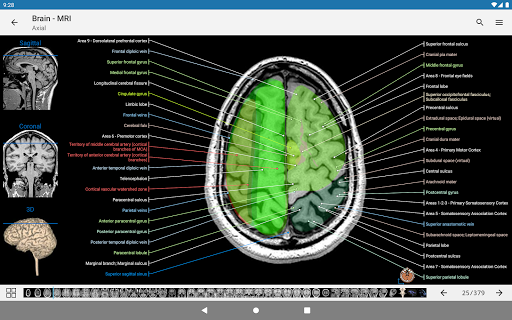

- وحدتان جديدتان: الدماغ - TOF والأوعية الدموية الدماغية ، أطلس التشريح الوعائي العصبي الطبيعي لشرايين الدماغ على الأوعية الدموية الدماغية. - تم إعادة صياغة الواجهة. - تتوفر علامة تبويب جديدة باسم "QuickLinks" ، ترسل وحدات في أقسام من جسم الإنسان وتسمح لك بالسفر السريع إلى الوحدات التي تبحث عنها. الخلل الصغيرة الثابتة.

-يمكنك الآن استخدام Facebook أو Google لتسجيل الدخول إلى التطبيق. -وضع الممارسة متاح الآن في اللوحة الجانبية أثناء عرض وحدة نمطية. (سيتم استبدال أسماء الهياكل بالأرقام ويمكنك النقر عليها لعرضها) - إعادة تسمية وتسميات جديدة للشرايين التاجية لوحدة تصوير الأوعية التاجية والأشعة المقطعية التاجية. أصبحت المصطلحات التشريحية أكثر تكيفًا مع التسميات الوعائية وممارسة التصوير القلبي. الخلل الصغيرة الثابتة